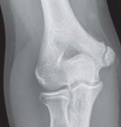

Elbow Pain

Roli Agrawal, MD; Sarah Kizilbash, MD; William Yaakob, MD

A 15-year-old boy presents with pain in the medial aspect of his right elbow that began 4 to 6 weeks earlier and progressively worsened.